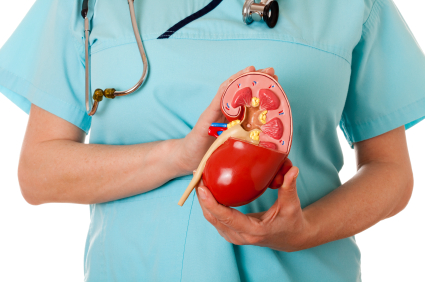

هر انسان دارای دو کلیه است که بزرگی هر یک به اندازه یک مشت است و هر کدام در یک طرف ستون فقرات در پایینترین سطح قفسه سینه قرار دارد. هر کلیه حدود یک میلیون واحد عملکردی به نام نفرون دارد. نفرون از واحد تصفیه کنندهی مویرگی به نام گلومرول تشکیل میشود که به توبول (لوله) متصل میشود. خون پس از ورود به گلومرول تصفیه میشود و مایع باقیمانده از توبول عبور میکند. در توبول آب و مواد شیمیایی بر حسب نیاز بدن به این مایع تصفیه شده اضافه یا از آن گرفته میشود و در نهایت فراوردهای به نام ادرار به دست میآید که باید از بدن دفع شود.

تشخیص

پزشک سابقه پزشکی بیمار را به طور کامل بررسی میکند و معاینه دقیقی انجام میدهد. همچنین پزشک دستور آزمایش خون و ادرار را برای به دست آوردن اطلاعات بیشتر درباره عملکرد کلیه میدهد.

هر انسان دارای دو کلیه است که بزرگی هر یک به اندازه یک مشت است و هر کدام در یک طرف ستون فقرات در پایینترین سطح قفسه سینه قرار دارد. هر کلیه حدود یک میلیون واحد عملکردی به نام نفرون دارد. نفرون از واحد تصفیه کنندهی مویرگی به نام گلومرول تشکیل میشود که به توبول (لوله) متصل میشود. خون پس از ورود به گلومرول تصفیه میشود و مایع باقیمانده از توبول عبور میکند. در توبول آب و مواد شیمیایی بر حسب نیاز بدن به این مایع تصفیه شده اضافه یا از آن گرفته میشود و در نهایت فراوردهای به نام ادرار به دست میآید که باید از بدن دفع شود.